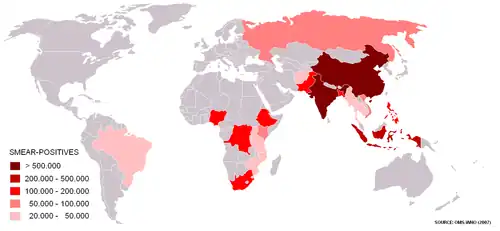

Voorkomen

Wereldwijd komt 80% van de tuberculosepatiënten in zes landen voor: China, India, Zuid-Afrika, Nigeria, Indonesië en Pakistan. De Wereldgezondheidsorganisatie WHO schat dat in 2015 wereldwijd 10,4 miljoen mensen tuberculose kregen en dat 1,8 miljoen mensen overleden ten gevolge van deze ziekte. Dit zijn circa 5.000 doden door tuberculose per dag. Ongeveer een derde van de wereldbevolking is met tbc-bacteriën besmet zonder ziek te zijn. Deze mensen hebben een latente tuberculose infectie, vaak afgekort tot LTBI. Het is van belang dit te onderscheiden van de actieve tuberculose, de tuberculose als ziekte. Het is niet altijd even duidelijk of een tbc actief is of dat het gaat om een oude infectie met tbc-bacteriën.

MDR-TB wordt vooral gevonden in gedeelten van Oost-Europa,[17] Kazachstan,[18] Kirgizië, in Israël door immigratie uit Rusland, Zuid-Afrika, China en onder meer Haïti en India. Gevangenissen zijn in veel landen berucht vanwege de grote aantallen tbc-patiënten. Wereldwijd zijn er jaarlijks ongeveer 500.000 nieuwe MDR-TB-patiënten, dit is 5% van alle nieuwe tuberculosegevallen per jaar.[16] Wereldwijd krijgt maar een op de vijf MDR-TB patiënten de juiste behandeling. In 2009 zouden er in Kirgizië 1400 lijders aan MDR-TB zijn geweest, van wie er slechts 600 onder behandeling waren en van wie er 300 gevangenen waren. De behandeling kostte daar ongeveer 7000 Amerikaanse dollar per patiënt, een groot bedrag in een land waar het gemiddeld jaarloon 1600 dollar bedraagt.